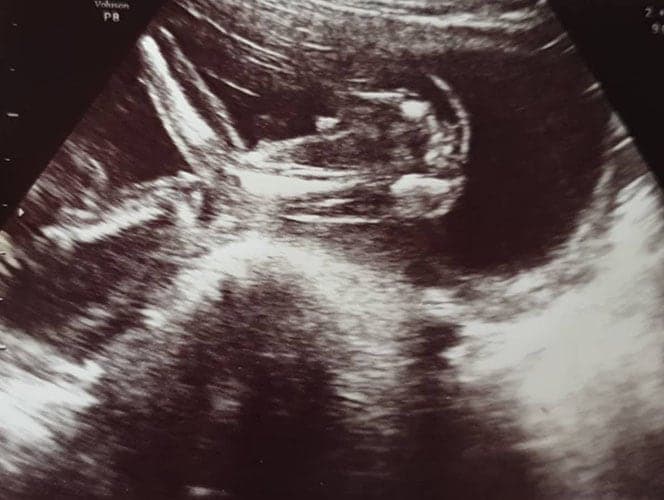

Ultraschallbilder aus dem 2. Trimester (13. bis 28. SSW)

Im 2. Trimester bekommt man oft die schönsten "Ganz-Körper" Ultraschallbilder. Das Baby ist nun so groß, dass man alles gut erkennen kann und noch nicht zu groß, so dass es noch ganz auf das Bild passt. In dieser Zeit lässt sich meist das Geschlecht bestimmen, wobei manche Babys es einfach nicht preis geben wollen und sich immer so drehen, dass man nichts erkennen kann.